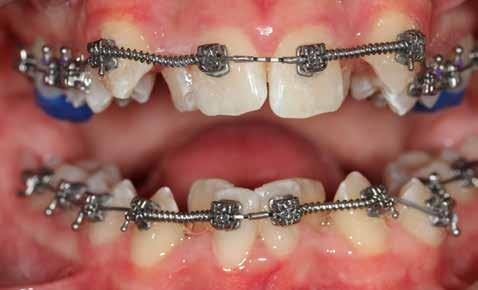

Ebben a cikkben egy 16 éves lánypáciens esetét szeretném bemutatni (1–7. képek)

A Pitts21-es fix készülékes kezelés során a harapásemelőket a felső nagyőrlő fogakra ragasztottuk, hogy a felső molárisok intrúziójával segítsék a harapás zárását (8. kép) Ún. keresztharapásos, majd később normál class 2-es gumihúzással (9–10. képek), továbbá az elülső fogakon alkalmazott ún. Rainbow harapás-záró gumihúzással (11. kép) korrigáltuk a jobb oldali teljes premolárisnyi distal-harapást, valamint az elülső nyitott harapást.

6 hónap után a nyitott harapás már nagyjából összezárásra került (12. kép)! A gumihordás a kezelés teljes hosszában folyamatos, éjjel-nappal, 22-24 órában az étkezések és az utánuk történő fogmosás kivételével.

A fix fogszabályozó készülék mindössze 16 hónapos kezelés után került eltávolításra! Páciensünk legnagyobb örömére állcsontműtét nélkül sikerült mind az arcesztétikai, mind a funkcionális rehabilitáció (13–18. képek)